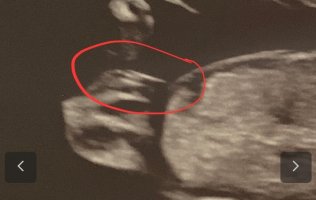

Har også lest om nub teorien men synes det er vanskelig å vite, også har jeg lest at den er 40-60 % riktig. Klarer du å se noe her?☺️ Var 12+5 når UL ble tatt. Tror kanskje legen kunne se hva det var, men ville ikke si noe. Sa at det var bedre å vente til OUT

Nub teorien er 98% i uke 13. Dette er hva alle uktralydteknikere baserer sine uttalelser om kjønn på inntil pung eller kjønnslepper blir synlige. En høy nub med stacking er aldri en jente.

Men din baby derimot tror jeg er en jente. Veldig lang nub og den er helt rett. Kan enda løfte seg, men tviler på det utifra hvor lang denne er.